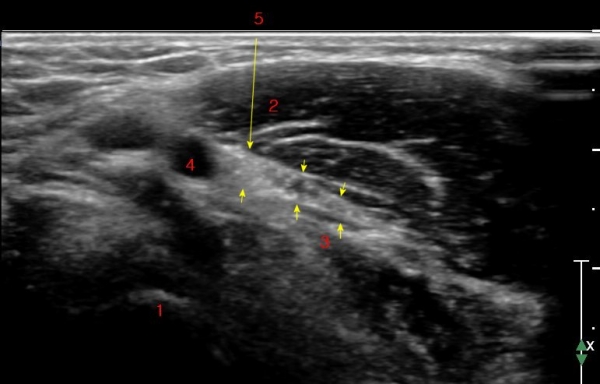

ÃÊÀ½ÆÄ °Ë»ç : ȸ³»±Ù ±ÙÀ§ºÎ¿¡¼­ Á¤Á߽Űæ Ⱦ´Ü¸é°Å»ç¿¡¼­ ƯÀÌ ¼Ò°ßÀ» º¸ÀÌÁö ¾ÊÀ¸³ª(»çÁø 1) ȸ³»±Ù ¿ä°ñµÎ ±â½ÃºÎ

¿¡¼­  Á¤Á߽ŰæÀÇ ±¹°íÀû ¾Ð¹Ú ¹× ÆíÆòÈ­°¡ °üÂûµÊ(»çÁø 2). ÀÌ·± º¯È­´Â °ÇÃø(»çÁø 5)°ú ºñ±³Çϸé

¶Ñ·ÇÇÔ.

Á¤Á߽Űæ Á¾´Ü¸é°Ë»ç¿¡¼­ ȸ³»±Ù ¿ä°ñµÎ ±â½ÃºÎ¿¡¼­ Á¤Á߽ŰæÀÇ ±¹¼ÒÀû ¾Ð¹Ú°ú Ç¥ÃþÀ¸·Î ÀüÀ§°¡

°üÂûµÇ°í ¾Ð¹ÚÀÇ ±ÙÀ§ºÎ¿¡¼­´Â Á¤Áß½Å°æ ºÎÁ¾ÀÌ °üÂûµÊ(»çÁö 3).

ÀÌ·± º¯È­´Â °ÇÃø(»çÁø 6)°ú ºñ±³ÇÏ¸ç ¶Ñ·ÇÇÔ.